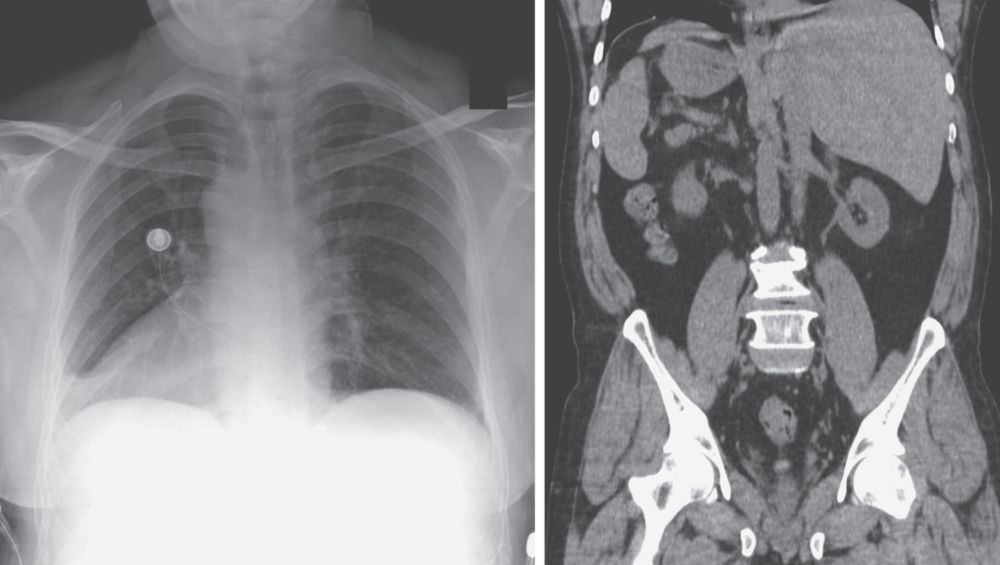

A 66-year-old man presented to the emergency department with a 3-day history of cough, congestion, and pain in his chest and on the left side of his abdomen.

What is the abnormality noted incidentally on chest radiograph and computed tomography of the abdomen?